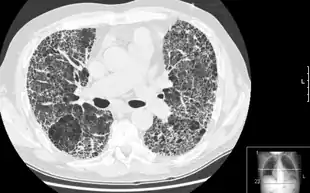

| Other names: Interstitial pulmonary fibrosis | |

| A chest X-ray demonstrating pulmonary fibrosis believed to be due to amiodarone. | |

Pulmonary fibrosis is suggested by a history of progressive shortness of breath (dyspnea) with exertion. Sometimes fine inspiratory crackles can be heard at the lung bases on auscultation. A chest X-ray may or may not be abnormal, but high-resolution CT will frequently demonstrate abnormalities.[3]